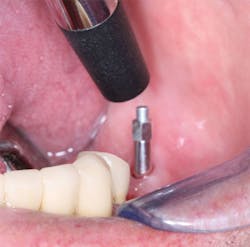

Figure 3: What resistance will this osteotomy provide to implant placement? Assuming the clinician has set the torque of the implant placement motor correctly, and the implant goes into the bone with the amount of torque at which the motor is set, the clinician may make a good estimation about the timing for implant loading.

Figure 4: On screwing the implant into place, bone density or lack of it is obvious.